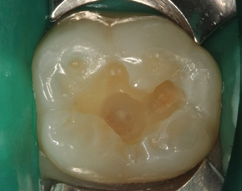

Bei dem 57-jährigen Patienten imponierte in der Routine-Bissflügelaufnahme eine Sekundärkaries an dem mit einem Gold-inlay versorgten Zahn 14 (Abb. 1). Der vitale und symptomfreie Zahn zeigte lediglich radiologisch (Abb. 2) einen Randdefekt distal sowie den Verdacht auf Karies unter dem Befestigungs- bzw. Unterfüllungszement. Nach Entfernung des Goldinlays ergab sich der Verdacht auf eine Pulpaeröffnung (Abb. 3). Klinisch war keine Blutung feststellbar, was allerdings durch die Lokalanästhesie kaschiert sein konnte. Aufgrund der Symptomlosigkeit des Zahnes und fehlender Anzeichen einer Pulpitis (fehlende Blutung) sowie einer Nekrose (erhaltene Vitalität) fiel die Entscheidung zugunsten einer Vitalerhaltung unter Beibehaltung eines engmaschigen Recalls mit Vitalitätsproben. Die Überkappung der Eröffnungsstellen erfolgte als Alternative zu Calciumhydroxid [8] mit einem Portlandzement enthaltenden Flowkomposit mit hohem pH-Wert [7,51] (TheraCal LC, Bisco, Abb. 4). Obwohl dieses Produkt hinsichtlich seiner Effektivität und Zelltoxizität nicht an ProRoot MTA (Dentsply Sirona) und Biodentine (Septodont) [42] herankommt [5,11], ist es hinsichtlich seiner Praktikabilität und der Möglichkeit des sofortigen, zügigen Weiterarbeitens konkurrenzlos. Ein vergleichbares Produkt gibt es z.B. bei Ultradent (Ultra- Blend Plus).